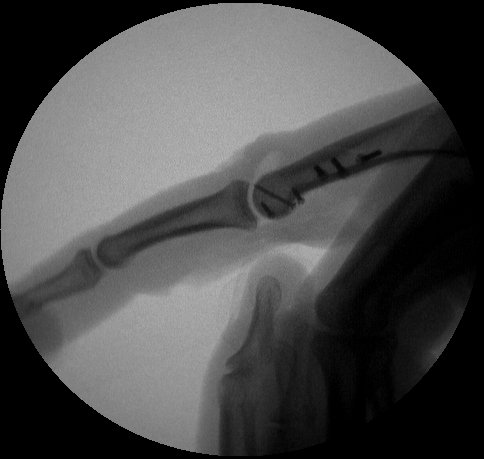

Intraoperative fluoroscopy.